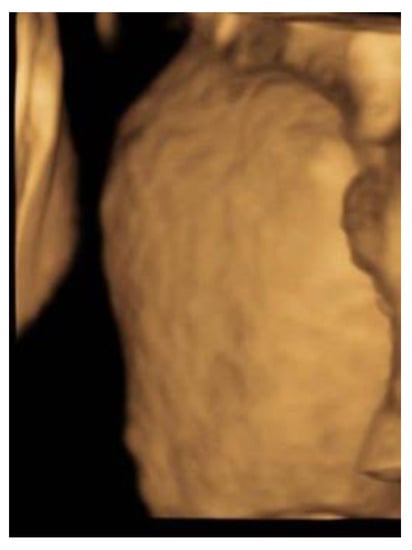

A 27-year-old primigravida was referred to the outpatient clinic of our hospital at a gestational age (GA) of 17 + 3 weeks following detection of a fetal unilateral hydronephrosis by the peripheral gynecologist. Ultrasonography demonstrated a duplex collecting system in the left kidney with hydronephrosis of the cranial pole, moderate dilatation of the upper pole ureter, and mild dilatation of the lower pole ureter. The cerebellum at that time showed a minimal posterior curving (

Figure 1), but no distinct banana-sign. Inspection of the spine was inconspicuous. The patient was reevaluated in our center at 24 weeks GA. The hydronephrosis of the upper pole of the left kidney remained stable. However, the cerebellum presented a banana-shape with herniation of the hindbrain onto C2 and minimal lemon-sign of the skull (

Figure 2). The lateral ventricles were not dilated. Ultrasound examination of the spine revealed a closed skin except for a minimal fistula in the sacro-coccygeal region (